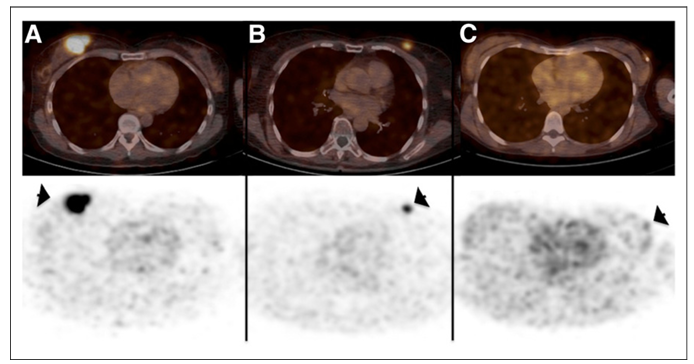

圖三、PET/CT 圖像(上圖)和 PET 圖像(下圖)顯示原發(fā)性乳腺癌病灶(箭頭)中68-GaNOTA-Anti-HER2 VHH1的攝取。(A) 14號患者的示蹤劑攝取最高(SUV 平均值,11.8)。(B) 15號患者顯示中度示蹤劑攝取,仍具有很高的腫瘤-背景比(SUV 平均值,4.9)。(C)6號患者成像結果顯示沒(méi)有攝?。⊿UV 平均值,0.9),CT圖像的腫瘤區域用箭頭指示。

HER2 納米抗體示蹤劑68-GaNOTA-Anti-HER2 VHH1在I期臨床試驗中取得了令人鼓舞的結果,68-GaNOTA-Anti-HER2 VHH1在腫瘤中的積累水平明顯超過(guò)了背景值,且在HER2 陽(yáng)性轉移灶中有高積累。因此,該示蹤劑順利進(jìn)入了II 期臨床研究,目的是評價(jià)乳腺癌患者腦轉移瘤對該示蹤劑的攝取情況 (圖三)(NCT03331601)3?;?8-GaNOTA-Anti-HER2 VHH1的優(yōu)良性能,Precirix公司進(jìn)而開(kāi)發(fā)了[131I]-SGMIB Anti-HER2 VHH1示蹤劑,現正在進(jìn)行臨床I 期試驗,旨在評價(jià)該示蹤劑的安全性、耐受性及有效劑量(NCT02683083)4。此外,另一款納米抗體成像劑99mTc-NM-02正在進(jìn)行I期臨床研究 (NCT04040686)5,10位乳腺癌患者注射 3-12 MBq/kg 99mTc-NM-02, 無(wú)不良反應報道,且99mTc-NM-02的攝取與HER-2的表達呈正相關(guān)。近期,北京大學(xué)臨床腫瘤學(xué)院研發(fā)的99mTc-MIRC208也正在臨床實(shí)驗中,共有200位受試者,旨在研究納米抗體示蹤劑99mTc-MIRC208對HER2陽(yáng)性患者成像的可行性及特異性(NCT04591652)。